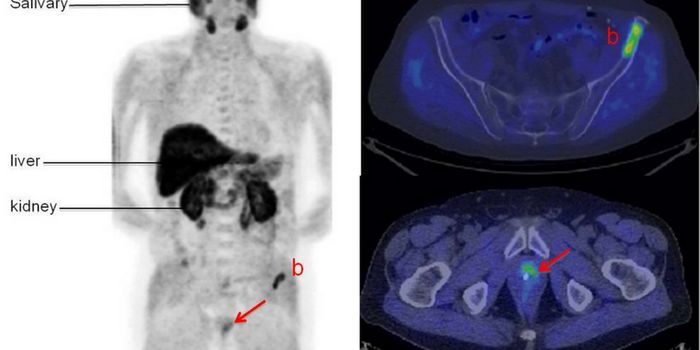

JUN 29, 2017Chemistry & PhysicsDuring its annual member meeting in June the Society of Nuclear Medicine and Molecular Imaging, an international body th ...